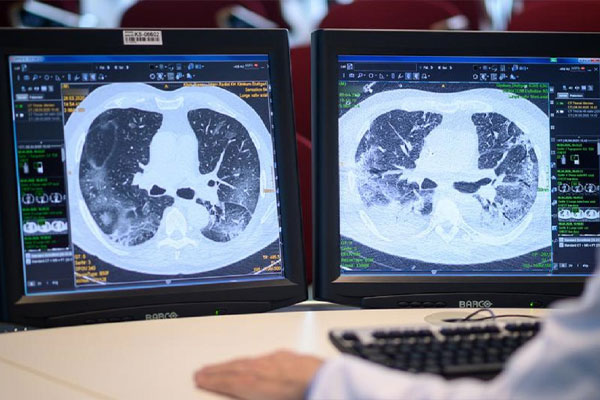

نمای گرند گلس در سی تی اسکن ریه

نمای گرند گلس یا ggo در سی تی اسکن ریه یکی از نماهای شایع در انواع بیماری های ریوی می باشد. در نمای گرند گلس انگار بافت ریه از پشت یک شیشه مات دیده میشود. بافت ریه کدر دیده می شود. دوره تفسیر سی تی اسکن ریه آنلاین مِد

نمای ggo ام به صورت دیفیوز و هم فوکال دیده می شود . یعنی هم ممکن ایت بخش اعظمی از ریه را درگیر کرده باشد و هم به صورت نقطه ای و فوکال باشد.

همانطور که گفتیم نمای ground-glass opacity (GGO) دقیقا شبیه آن است که شما بافت ریه را از پشت یک شیشه مات در سی تی اسکن ببینید!

طبق گفته در نمای ggo شما بافت ریه را کدر میبینید!